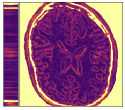

In Figure 12 we compare the PD3O reconstructions (top) and their corresponding errors with respect to the ground truth (bottom) using different regularization parameter choices , and for PD3O. Obviously, using the estimated parameter-map leads to a significant improvement of the reconstruction. In particular, sharp edges are retained, while using a constant regularizing parameter results in a significant blur. This can be also seen in Table 4, where we compare the NRMSE, PSNR, SSIM and blur and evaluated on the first 100 test images of the LoDoBaP dataset. These results are visualized in Figure 13 using box-plots. Note that the FBP seems to better than PD3O- in terms of the blur effect, but this can be explained by the fact that FBP reconstructions admit a lot of high-frequency artefacts leading to a small blur effect.

Further PD3O- reconstructions with their corresponding estimated parameter-maps are shown in Figure 14. Note that the parameter-maps are given in a logarithmic scale. As expected, the regularization is strong in constant areas and less strong on edges or finer details in order to reduce a smoothing in these regions.